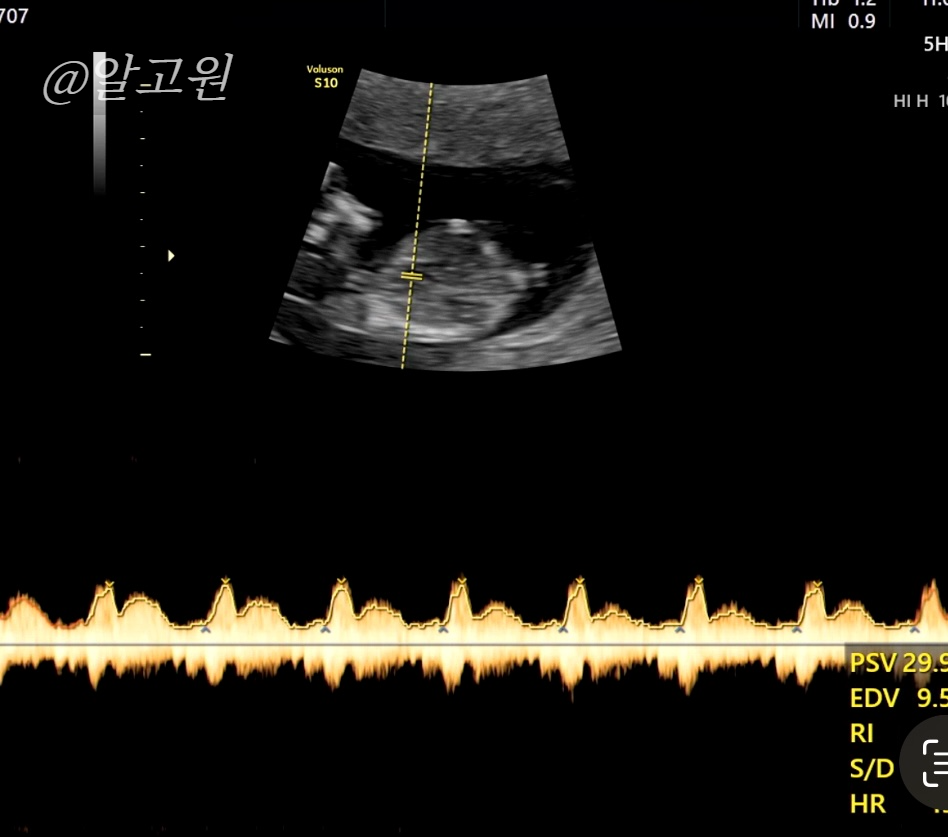

초음파로 목투명대, 척추와 뼈, 장기, 뇌 모양, 심장박동소리, 태반 위치 등

선생님께서 아주 꼼꼼히 봐주십니다.

다행히도 유동이는 정상,정상,정상!